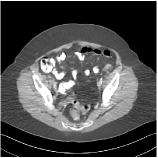

We have conducted experiments on 20 test slices (slice 20, slice 50, slice 100, slice 150 and slice 200 of patient L067, L143, L192, L310) of the Mayo Clinic data. Table I shows the averaged image quality of 20 test images with different methods. From Table I, we observe that Parallel SUPER significantly improves the image quality compared with the standalone methods. It also achieves 1.8 HU better average RMSE compared with Serial SUPER while its SSIM is comparable with Serial SUPER. Fig. 3 shows the reconstructions of L067 (slice 50) and L310 (slice 150) using PWLS-ULTRA, FBPConvNet, serial SUPER (FBPConvNet + PWLS-ULTRA), and parallel SUPER (FBPConvNet + PWLS-ULTRA), along with the references (ground truth). The Parallel SUPER scheme achieved the lowest RMSE and the zoom-in areas show that Parallel SUPER can reconstruct image details better.